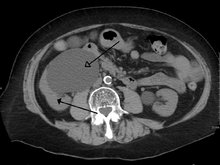

Imaging studies, such as an intravenous urogram (IVU), ultrasound, CT or MRI, are also important investigations in determining the presence and/ or cause of hydronephrosis. Whilst ultrasound allows for visualisation of the ureters and kidneys (and determine the presence of hydronephrosis and / or hydroureter), an IVU is useful for assessing the anatomical location of the obstruction. Antegrade or retrograde pyelography will show similar findings to an IVU but offer a therapeutic option as well. Real-time ultrasounds and color-flow Doppler tests in association with vascular resistance testing helps determine how a given obstruction is effecting urinary functionality in hydronephrotic patients.[12]

The choice of imaging depends on the clinical presentation (history, symptoms and examination findings). In the case of renal colic (one sided loin pain usually accompanied by a trace of blood in the urine) the initial investigation is usually a spiral or helical CT scan. This has the advantage of showing whether there is any obstruction of flow of urine causing hydronephrosis as well as demonstrating the function of the other kidney. Many stones are not visible on plain X-ray or IVU but 99% of stones are visible on CT and therefore CT is becoming a common choice of initial investigation. CT is not used however, when there is a reason to avoid radiation exposure, e.g. in pregnancy.

For incidentally detected prenatal hydronephrosis, the first study to obtain is a postnatal renal ultrasound, since as noted, many cases of prenatal hydronephrosis resolve spontaneously. This is generally done within the first few days after birth, although there is some risk that obtaining an imaging study this early may miss some cases of mild hydronephrosis due to the relative oliguria of a newborn. Thus, some experts recommend obtaining a follow up ultrasound at 4–6 weeks to reduce the false-negative rate of the initial ultrasound.[14] A voiding cystourethrogram (VCUG) is also typically obtained to exclude the possibility of vesicoureteral reflux or anatomical abnormalities such as posterior urethral valves. Finally, if hydronephrosis is significant and obstruction is suspected, such as a ureteropelvic junction (UPJ) or ureterovesical junction (UVJ) obstruction, a nuclear imaging study such as a MAG-3 scan is warranted.